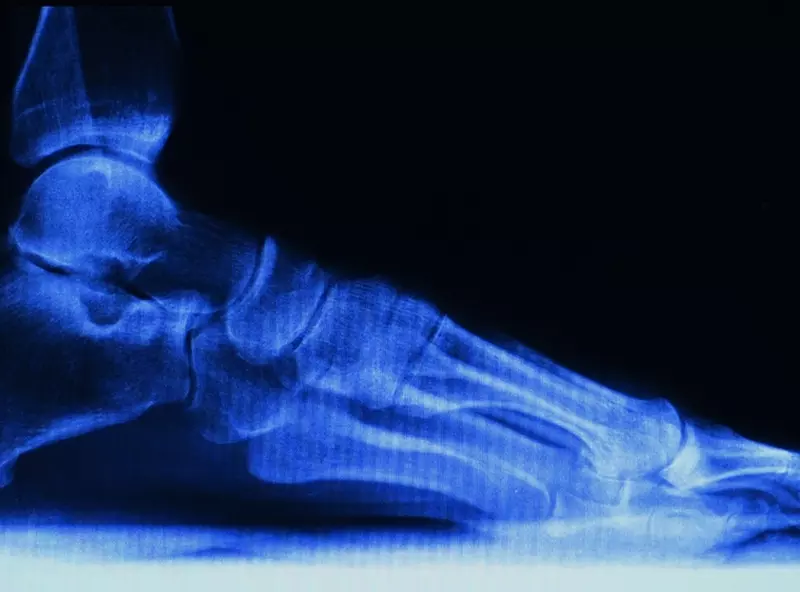

Połączenie czaszkowo-szyjne (cranio-cervical junction – CCJ) w sensie dosłownym tworzy ruchome przejście pomiędzy kłykciami kości potylicznej (C0) i powierzchniami stawowymi pierwszego kręgu szyjnego – atlasu (C1), ale ze względu na skomplikowaną biomechanikę ruchu w górnym piętrze szyjnym, specyfikę budowy dwóch górnych kręgów oraz specyfikę unerwienia tego rejonu, przejście czaszkowo-szyjne należy omawiać łącznie z trzema górnymi segmentami kręgów szyjnych. Strefa ta należy do najbardziej skomplikowanych ruchomych połączeń szkieletu. Przy znacznej ruchomości, jaką zapewnia, musi jednocześnie sprostać ochronie przed uszkodzeniem tak ważnych struktur, jak rdzeń przedłużony, rdzeń kręgowy, tętnice kręgowe, opony rdzenia kręgowego – stąd niespotykane w innych rejonach nagromadzenie więzadeł i błon łącznotkankowych oraz krótkich mięśni przebiegających wielowarstwowo w dość ciasnej przestrzeni.

Struktury kostne przejścia czaszkowo-szyjnego tworzą od góry kłykcie potyliczne zawierające wypukłe powierzchnie stawowe ustawione pod kątem 30° do płaszczyzny poprzecznej i skierowane na zewnątrz, od dołu zaś pasujące do nich wklęsłe powierzchnie stawowe umiejscowione na masach bocznych atlasu. Połączenie to wzmocnione torebką stawową i membraną potyliczno-szczytową pozwala na ruch kości potylicznej względem atlasu w trzech płaszczyznach: strzałkowej (zgięcie/wyprost), czołowej (boczne zgięcie) i poprzecznej (rotacja). Oczywiście istnieje również pewna swoboda ruchu w kierunku trakcji i kompresji co zapewnia efekt amortyzacyjny. Zakres ruchu w każdej z tych płaszczyzn nie przekracza 3–5°, co wydaje się nieproporcjonalne do możliwości wynikających z samego kształtu powierzchni stawowych [1, 2].